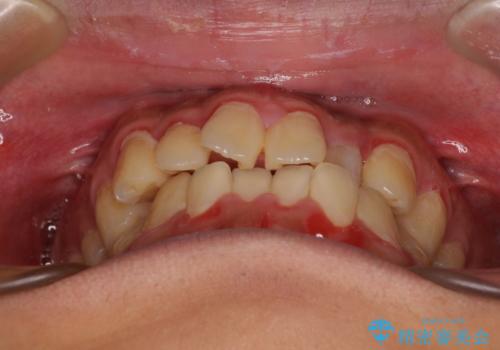

- 前歯のデコボコとクロスバイトを気にして来院された患者様です。

クロスバイトはありましたが、叢生の程度としては酷くなかったため、ワイヤー矯正でもマウスピース矯正でも、好きな方を選択していただきました。

治療開始前は汚れが多く、全体的に歯肉が腫れていましたが、矯正治療を通して腫れも少しずつ改善されました。